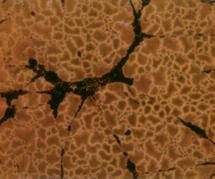

Nella figura A è possibile vedere la struttura del tessuto di un seno non predisposto per l’allattamento, caratterizzato dalla struttura densa di tessuto connettivo che circonda il condotto del latte, al centro dell'immagine, in gran parte chiuso.

In netto contrasto, la figura B mostra la struttura cellulare di un seno predisposto all’allattamento, caratterizzato da tessuto connettivo lasso, la presenza di cellule della ghiandola principale necessaria per la produzione di latte (piccoli cerchi bianchi), nonché il condotto del latte ampiamente aperto (al centro dell'immagine).

A. Condotto del latte (chiuso) nel tessuto del seno in condizioni normali

B. Condotto del latte (aperto) durante l’allattamento

A Ripresa di un condotto del latte al microscopio, sito in un seno non predisposto all’allattamento (chiuso)

B. In funzione dell’allattamento si ristruttura il tessuto mammario. Il condotto è aperto e il latte può uscire.